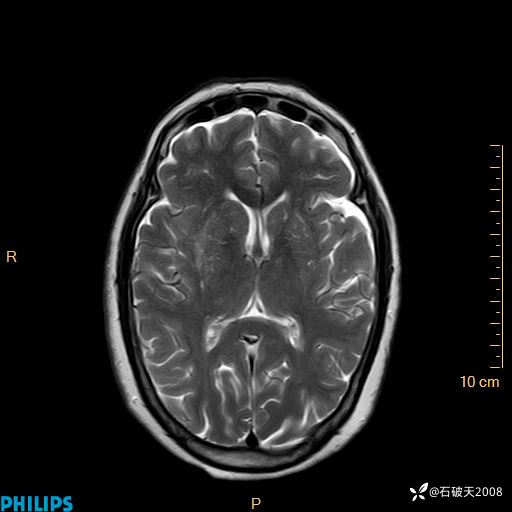

2020.11.14MR

DWI